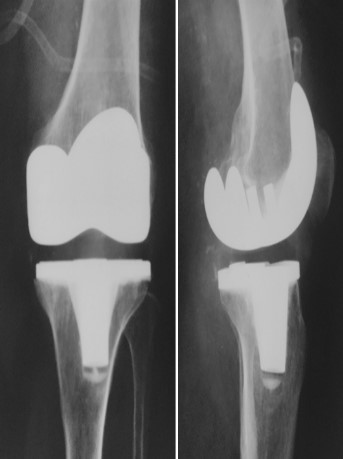

Приклад 2. Хвора  М. 68 років. Діагноз: лівобічний деформівний IVст. гонартроз, стан після ТЕП лівого КС (2014р.). Під час виконання оперативного втручання компоненти ендопротезу встановлені в варусному положенні. Асептична нестабільність компонентів ендопротеза, тотальна  нестабільність зв’язкового апарату компонентів колінного суглоба (2017 р.)  Хворій виконано ревізійне ендопротезування: видалення компонентів ендопротезу, виявлений дефект виростку великогомілкової кістки тип Т2А за класифікацією АОRI [G.A. Engh, C.H. Rorabeck, 1997]. Враховуючи стан зв’язкового апарату використаний зв’язаний ендопротез типу Hinch.